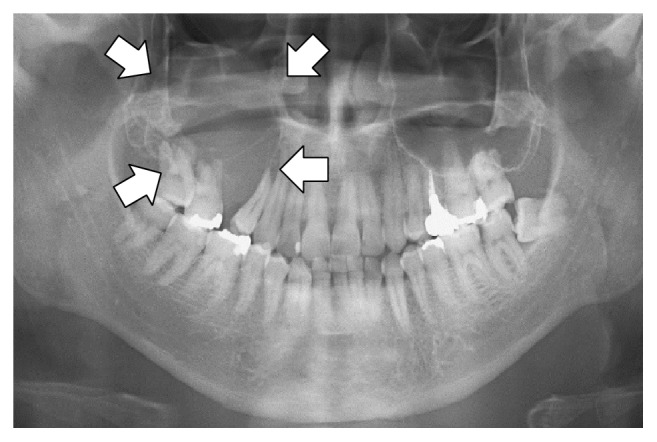

Vision Fine-tuning¶

Набор данных для точной настройки зрения или мультимодальной модели также включает в себя ввод изображений. Например, в Llama 3.2 Vision Notebook используется рентгенографический кейс, чтобы показать, как искусственный интеллект может помочь медицинским работникам более эффективно анализировать рентгеновские снимки, компьютерную томографию и ультразвук.

Мы будем использовать выборочную версию набора данных рентгенографии ROCO. Вы можете получить доступ к набору данных здесь. Набор данных включает рентгеновские снимки, компьютерную томографию и ультразвуковое исследование, демонстрирующие медицинские условия и заболевания. К каждому изображению есть подпись, написанная экспертами с описанием. Цель состоит в том, чтобы точно настроить VLM, чтобы сделать его полезным инструментом анализа для медицинских работников.

Давайте взглянем на набор данных и проверим, что показывает первый пример:

| Image | Caption |

|---|---|

|

Panoramic radiography shows an osteolytic lesion in the right posterior maxilla with resorption of the floor of the maxillary sinus (arrows). |